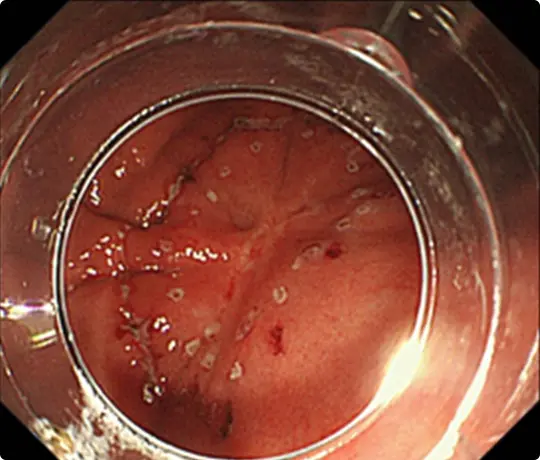

約4cmの高度な線維化を伴う早期大腸がんに対するESDを提示します。当科で考案したUnderwater ESD(生理食塩水の中で行うESD)が有効でした。

重症の潰瘍性大腸炎の既往があり、高度な線維化により難易度が高いと予想されました。

粘膜の下に液体を注入して病変を浮かせます。

病変の外側の粘膜を電気メスで切開したところです。

粘膜の下の組織(粘膜下層)を電気メスで剥がそうとしていますが、高度な線維化で筋層との境界がよく分かりません。このままでは筋層を傷つけて穴をあけてしまうリスクがあります。

当科で考案したUnderwater ESD(生理食塩水の中で行うESD)を行うことで光の反射がなくなり、拡大効果もあるため、鮮明な視野が得られ粘膜下層と筋層の境界が分かりやすくなります。筋層を傷つけないように、精密に剥離することが可能になります。

穿孔(壁に穴があくこと)などの問題なく、病変を切除しました。切除後は潰瘍が出来ますが、1~2ヵ月で治ります。

切除した検体をピンで伸ばしています。ホルマリンで固定後、病理診断を行います。病理診断で腫瘍は完全に切除されており、治癒と判定されました。